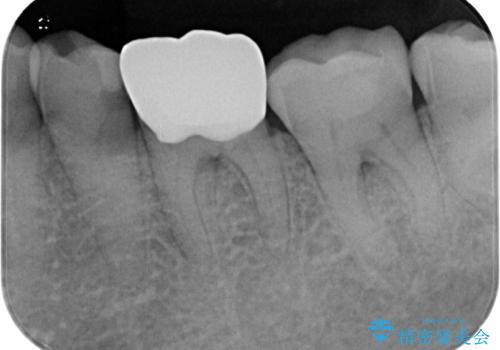

仮歯装着によりしみていた症状はおさまり、無事に治療を終えることができました。